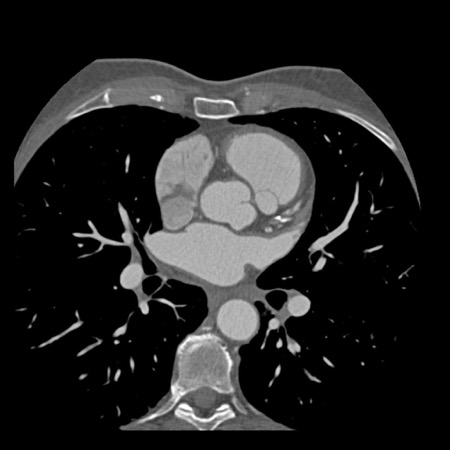

case 5 – CTA overestimates stenosis due to calcium

First, scroll through the CTA images.

How would you describe the findings on the coronary CTA?

Continue with the curved MPR images of the same patient.

The findings are:

- Long, partially

calcified plaque in the LM-LAD causing moderate stenosis (50-69%) (white